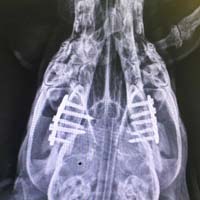

Yalıkavak veteriner kliniğimizde gerçekleştirdiğimiz ortopedik cerrahi uygulamalar:

Ortopedik cerrahi oldukça titizlik ve özen gerektiren cerrahi uygulamalardır. Diğer cerrahi disiplinlere nazaran asepsi ve antisepsi (sterilizasyon) konusunda ASLA hata kabul etmez. Eğer bu aşamada özensiz davranılırsa, postoperatif süreçte kemik dokunun iltihaplanmasına neden olup, kemiklerin kaynaması gecikmiş olur.